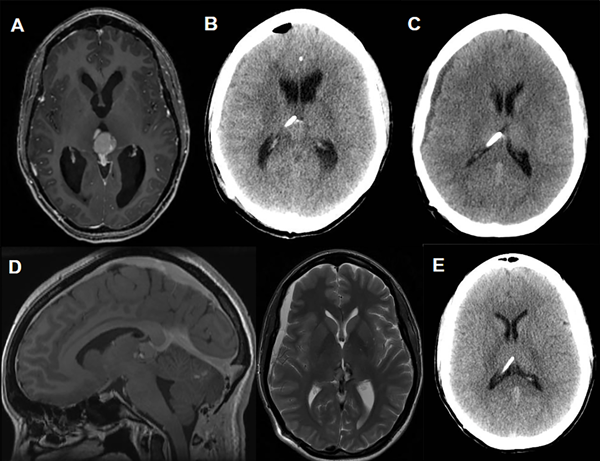

Caso 2 (Fig. 4)

Paciente femenina de 37 años de edad a quien, en contexto de diplopía y cefaleas, se le diagnostica un tumor del III ventrículo con hidrocefalia asociada (Fig. 4A). En este contexto se realizó una tercer ventriculostomía endoscópica con posterior exéresis tumoral. La anatomía patológica informó tumor del parénquima pineal con diferenciación intermedia. A los 15 días postoperatorios, por aumento de la hidrocefalia se decide la colocación de una VDVP Codman Hakim(R) a 140 mmH20 (Fig. 4B). En control por consultorios a los 10 días postoperatorios se evidencia higroma en TC de cerebro por lo que, en subsiguientes controles, se aumenta progresivamente la presión valvular hasta estabilidad imagenológica con reversión del higroma a 200 mmH20 (Fig. 4C - 4D). La paciente se encuentra actualmente estable, sin signos ni síntomas de hidrocefalia ni sobredrenado, con un seguimiento de 75 meses (Fig. 2D).

Figura 4. Caso 2.

Fig A. Resonancia magnética diagnóstica donde se evidencia lesión en región pineal, con intenso realce tras la administración de contraste, que asocia hidrocefalia obstructiva. Fig. B. Tomografía de encéfalo control a las 48 hs postoperatorias de la colocación de la VDVP. Fig. C. TC de cerebro a los 10 días postoperatorios con evidencia de higroma y consecuente aumento de la presión valvular a 170 mmH20. Fig. D. Corte sagital T1 con contraste y axial T2 de RM realizada al mes postoperatorio. Se evidencian signos de hipotensión de LCR (Realce paquimeníngeo, ingurgitación venosa, aplanamiento protuberancial y persistencia de dicha colección subdural). En este contexto se aumenta la presión valvular a 200 mmH20. Fig. E. TC realizada en el último control (follow up 75 meses) sin signos de sobredrenado.